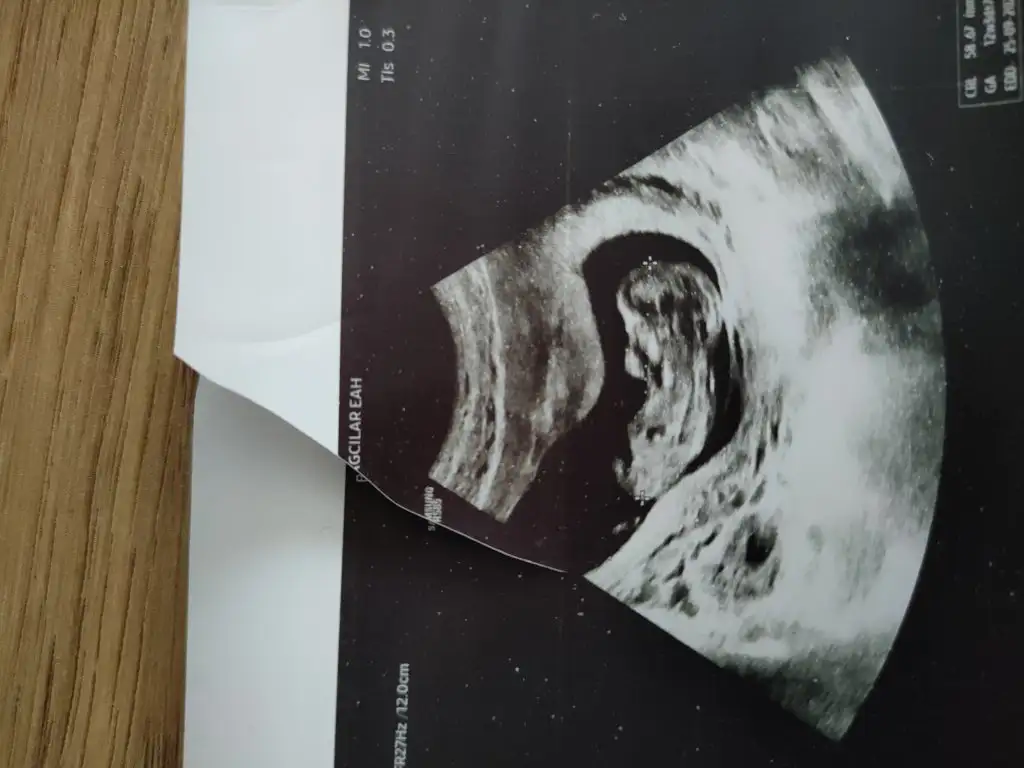

canım prenses gibi duruyorBenim büyük fotom yok dr un çıktı makinesi bozuk kağıtta verdi 9+3

Kız gibi canım, Allah sağlıcakla kucağına aldırsın inşallahCanım banada bakarmısın bakalım karındanDoktor bi tahminde bulundu sen ne diceksin diye merak ettim

5 ve 14. haftaya kadar olan ultrasyon fotolarınızı paylaşın. Vajinadan mı yoksa karından mı çekildiğini ve kaç haftalık olduğunu da mutlaka belirtin.

Not: Tahmin yaptığım anneler cinsiyet öğrendikten sonra lütfen bana geri dönüş yapın![]()

canım kaç haftalık?Ay bende bende lütfen(karından ultrason görüntüleri)